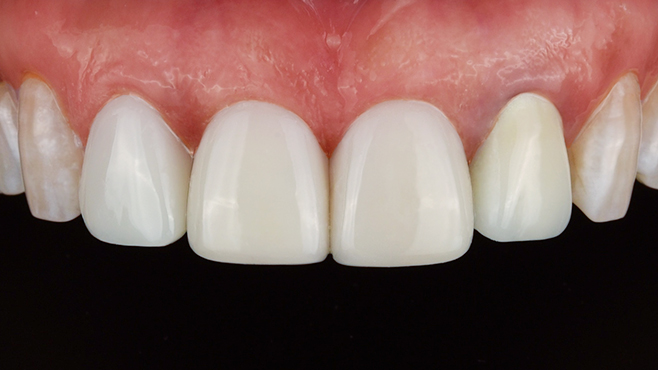

치과가 무서워 10년 동안 미뤄온 임플란트 수술 그 결과는?

2026.01.21